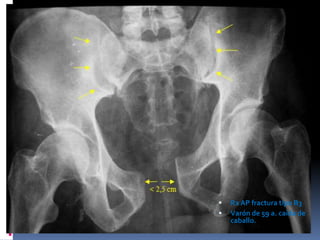

Fracturas tipo B-1, en libro abierto generadas por un mecanismo

de rotación externa o compresión anteroposterior. Son fracturas

con disrupción de la sínfisis del pubis e inestabilidad parcial del

anillo posterior.

RX AP: Fractura tipo B1.1 o en “libro abierto” del lado derecho.

Flechas blancas: disyunción píbica , fractura de la columna anterior del acetábulo que

se extendía al anillo obturador (flechas amarillas)